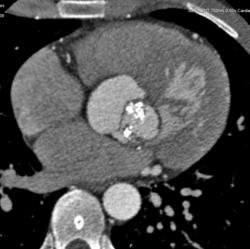

Мужчина 35 лет с клиникой стеноза аортального клапана. На КТ выявлен двустворчатый клапан с обызвествлениями в створках. Луковица аорты и восходящий отдел значительно расширены. Отмечается также вариант отхождения левой коронарной артерии - левая передняя нисходящая и огибающая отходят непосредственно от аорты. Правая коронарная артерия гипопластична.